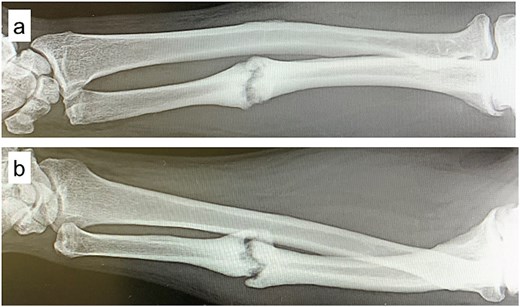

A 54-year-old man sustained a mid-diaphyseal ulnar fracture from a direct kick during karate practice. Initial conservative treatment at another hospital failed to achieve union over 12 months, and he was referred to our clinic with a diagnosis of nonunion. At presentation, he reported significant pain with a numerical rating scale (NRS) score of 6, and radiographs showed a 9 mm interfragmentary gap (Fig. 1a and b). Given his pain, we initiated proactive conservative management with prolotherapy, primarily targeting pain relief. Ultrasound revealed marked doppler signals at the nonunion site, suggesting inflammation and neovascularization. A mixture of 6 ml 50% dextrose and 4 ml 1% lidocaine (final 30% dextrose) was injected under ultrasound guidance into the neovascularized tissue and fracture gap (Fig. 2a and b). From the second session onward, bone healing had progressed to the point where the solution could no longer be injected between the bone fragments, so subsequent injections were administered around the periosteum. No restrictions were placed on weight-bearing or activity. Pain improved to NRS 4 at 2 weeks and to NRS 2 at 4 weeks, with early callus formation seen on radiographs. Prolotherapy was repeated five times at 2–3 week intervals. By 12 weeks, the patient was pain-free (NRS 0) and returned to karate. Radiographic union was confirmed at 15 weeks (Fig. 3a–d). Although initiated for pain control, prolotherapy led to relatively early bone union without surgery or complications.

Plain radiographs at initial presentation. (a, b) Nonunion at the mid-diaphysis of the ulna is observed.